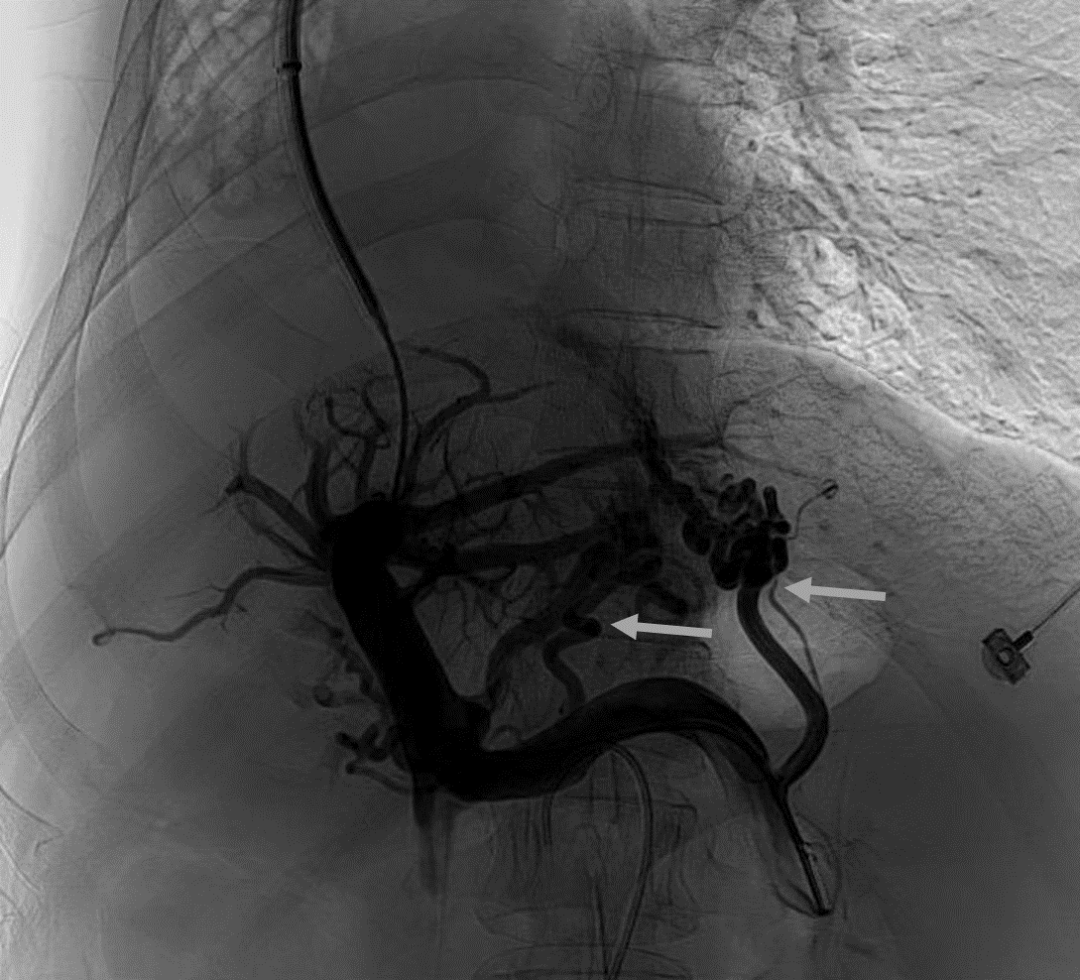

韓國宏教授介紹,TIPS手術(shù)是通過在肝靜脈與門靜脈之間的肝實質(zhì)內(nèi)建立分流通道,通過降低門靜脈壓力來預(yù)防和治療因門靜脈高壓引起的食管胃底曲張靜脈破裂出血或頑固性腹水。該手術(shù)不用開刀、創(chuàng)傷小、操作過程復(fù)雜、技術(shù)難度大、安全風(fēng)險高,是目前外周血管介入中難度最大的手術(shù)之一。再加上人群中右位心發(fā)病率極低(約萬分之一),經(jīng)查閱文獻,在國內(nèi)外尚未有類似病例報道,無經(jīng)驗參考。在右位心基礎(chǔ)上行TIPS術(shù),無疑是難上加難。我們反復(fù)研究患者肝臟及心血管的特殊情況,詳細討論了手術(shù)方案,決定放棄常規(guī)的肝靜脈穿刺,另辟蹊徑,選擇高難度高風(fēng)險的肝后段下腔靜脈穿刺門靜脈左支,憑借多年的經(jīng)驗和嫻熟的技術(shù)最終成功的在下腔靜脈與門靜脈之間放置了TIPS專用支架,術(shù)后門靜脈壓力梯度從術(shù)前的19mmHg降至3mmHg,曲張靜脈消失,解決了困擾曹女士多年上消化道出血的困擾?;颊咝g(shù)后第二天即可正常下床活動。